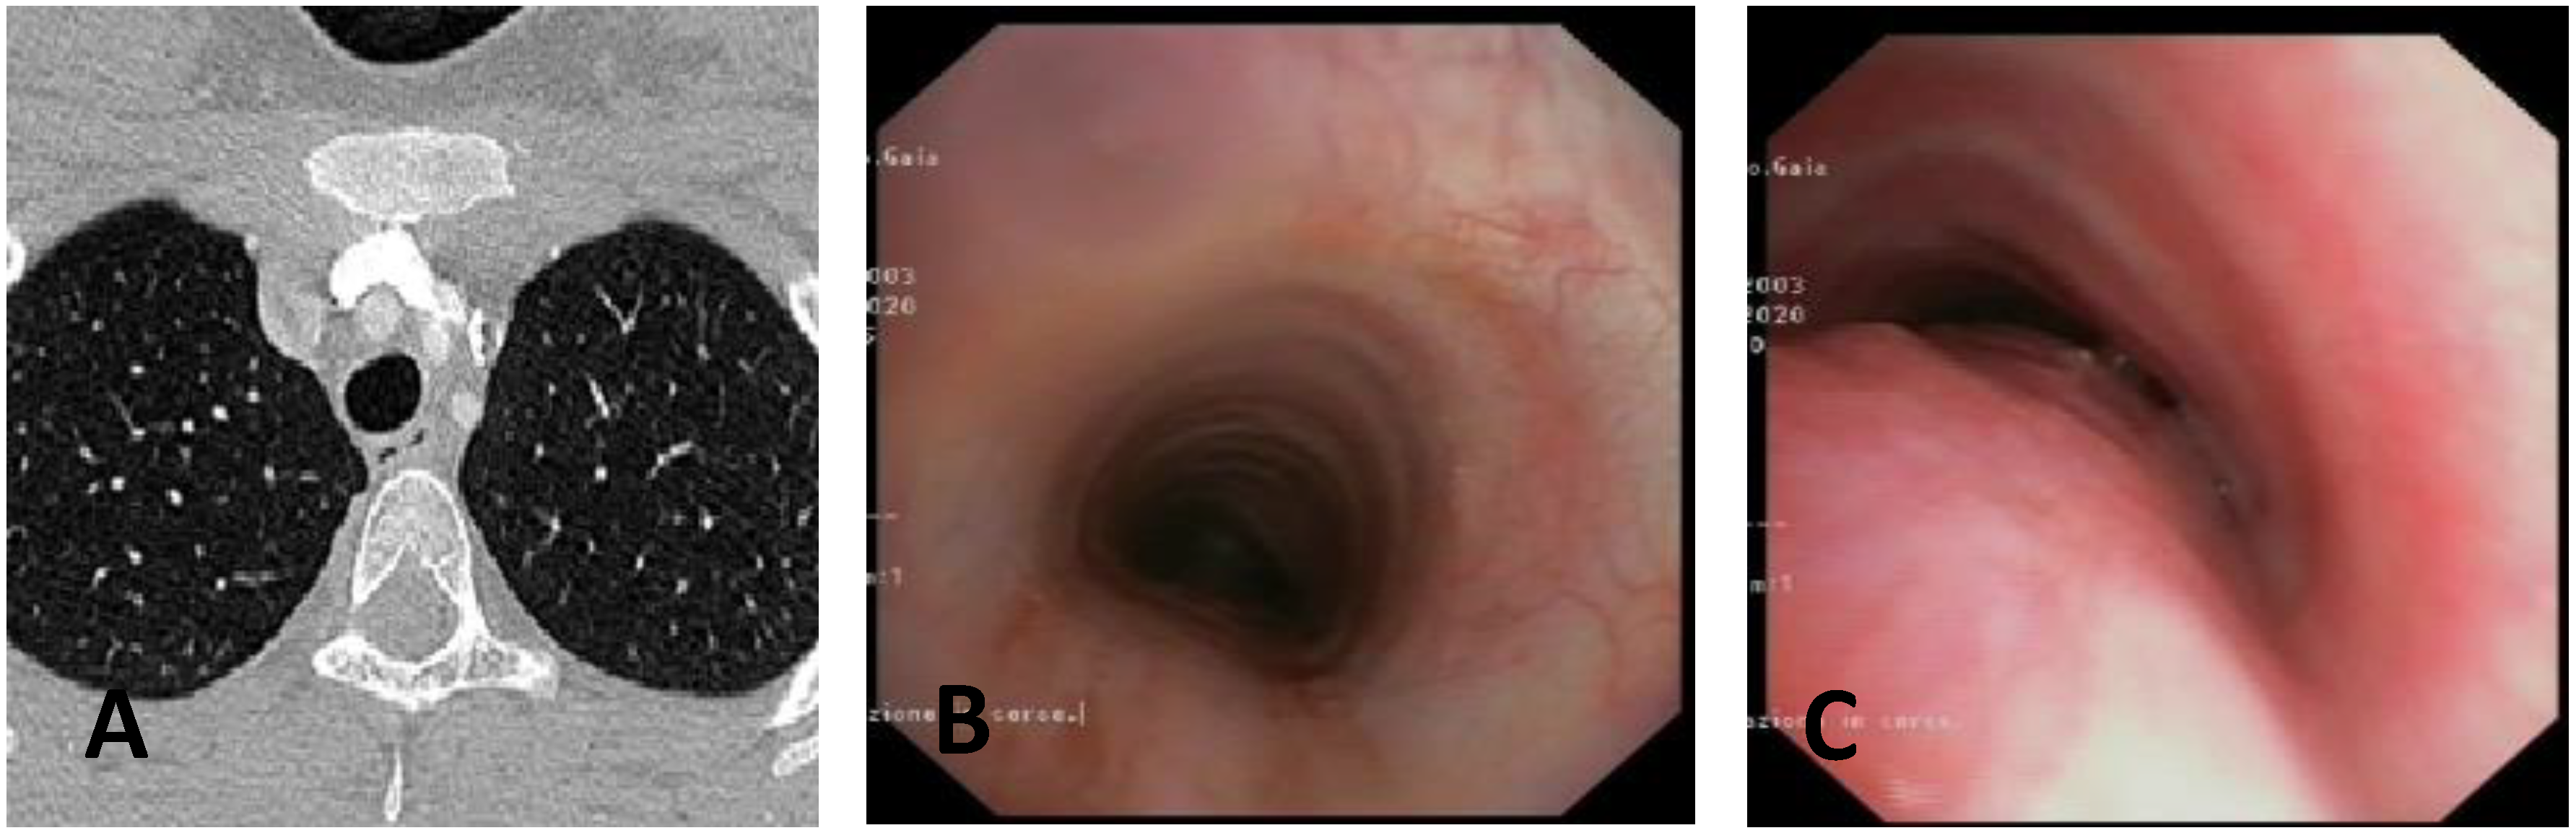

- Computed Tomography (CT): This is a continuously evolving imaging technique, rapid and non-invasive, providing an excellent overall view, independent of body size, with high spatial/temporal resolution. It allows multiplanar and volumetric reconstructions (MPR, MinPR, MipPR, and Volumetric 3D). It can be performed on children of all ages; anesthesia/sedation may be necessary under 5 years of age. Flash Monophasic Technique performed with a single scan, after intravenous injection of CM, provides information on airway morphology (but not dynamics), visualizing airways even distal to the site of obstructions and on mediastinal vessels exerting compression on the trachea or bronchi, highlighting any mediastinal pathology. CT shows cardiovascular anomalies compressing the airway, such as right aortic arch, complete/incomplete double aortic arch, pulmonary sling, and aberrant IA, all causing more or less severe TBM [16]. TM is very frequently associated with EA; CT can demonstrate malacia and extrinsic tracheal compression with a significant reduction in the tracheal ADP at the point of intersection with IA. CT can also demonstrate irreversible lung damage, such as bronchiectasis formation, caused by chronic recurrent lung infections resulting from reduced mucociliary clearance in TBM. Skeletal anomalies (e.g., pectus excavatum and scoliosis) that can cause airway compression and consequent TBM are also demonstrated. CT also evaluates tracheal compressions caused by space-occupying mediastinal lesions. Virtual bronchoscopy obtained with 3D airway reconstruction on CT images has not been very sensitive (<75%) in detecting TBM [17,18].

| Score: 2 | Reduction in the APD of the trachea between 75% and 90% compared to the suprastenotic tract and/or anterior tracheal wall and pars membranacea, tending to touch, without complete closure of the lumen, even when the patient performs abdominal straining, with poor representation of the cartilaginous rings. Figure 1, score 2 |